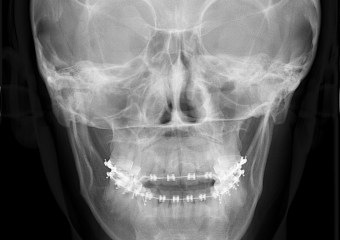

Telerradiografia Frontal após a cirurgia - Clínica Cliniface

Telerradiografia Frontal após a cirurgia